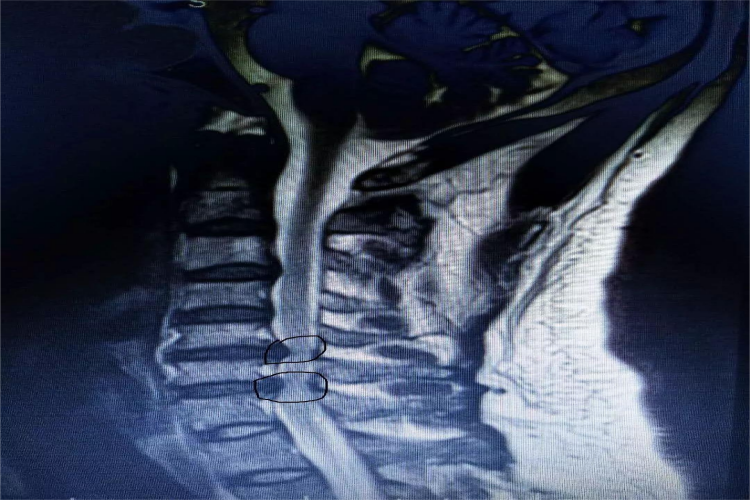

颈椎567突出指颈椎第5、6、7椎间盘突出,椎间盘突出节段的棘突间有时可有压痛。

颈椎567突出是由颈椎间盘退变,致使颈椎间盘突出症形成。

颈椎567突出即发生了颈椎间盘退变,后侧纤维环部分损伤或断裂,在轻微外力下可使颈椎过伸运动,致近侧椎骨向后移位,使椎间盘纤维环突然承受较大的牵张力,导致其完全断裂,髓核组织从纤维环破裂处经后纵韧带突入椎管,压迫脊髓和神经根而产生相应症状和体征。